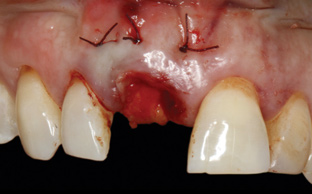

Prior to the initiation of the surgery, the surgical guide was tried in to confirm proper seating and stability (Figure 15). A flapless approach was not considered because the need for further bone grafting at the time of implant placement had been anticipated through the digital planning. A slightly palatal crestal incision was made, followed by two vertical incisions on the mesial and distal aspects of the edentulous site in order to preserve the papilla and avoid additional esthetic compromise to the anterior sextant. Next, a full-thickness flap was elevated to facilitate removal of the tenting screw and permit visualization of the buccal plate (Figure 16). A standard guided protocol was followed to place the implant, and its final position mirrored that of the digital plan. As predicted, the prosthetically driven implant position resulted in an insufficient buccal plate (Figure 17); therefore, additional guided bone regeneration was performed to reinforce the area and prevent future breakdown (Figure 18 and Figure 19). Making periosteal incisions could have compromised the blood supply to the flap, so instead, it was stretched in order to achieve tension free coronal advancement.31The flap was secured utilizing horizontal mattress sutures with additional supportive interrupted sutures to ensure primary closure (Figure 20). An immediate postoperative periapical radiograph (Figure 21) and CBCT scan (Figure 22) were taken, demonstrating a final implant position centered with the planned location of the gingival zenith.

(16.) Full-thickness flap elevation to expose the tenting screw and gain access for anticipated additional bone grafting following implant placement.

Figure 16

(17.) Implant placed 1-mm distal to the midline of the edentulous space, corresponding with the planned location of the gingival zenith. Note the lack of sufficient bone buccal to the implant that necessitated further grafting.

Figure 17